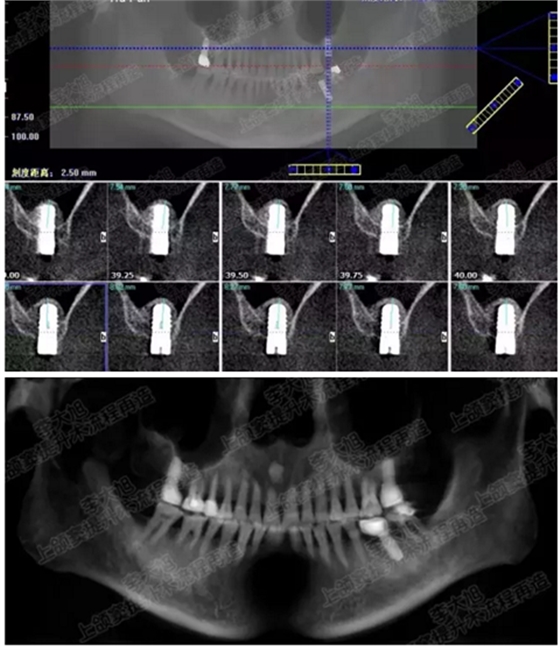

病例三

剩余骨量3mm

005.png

006.png

病例四

剩余骨量2mm-5mm且存在斜形竇底

007.png

提升8mm

008.png

009.png

病例五

剩余不足1mm

112.png

提升10mm

113.png